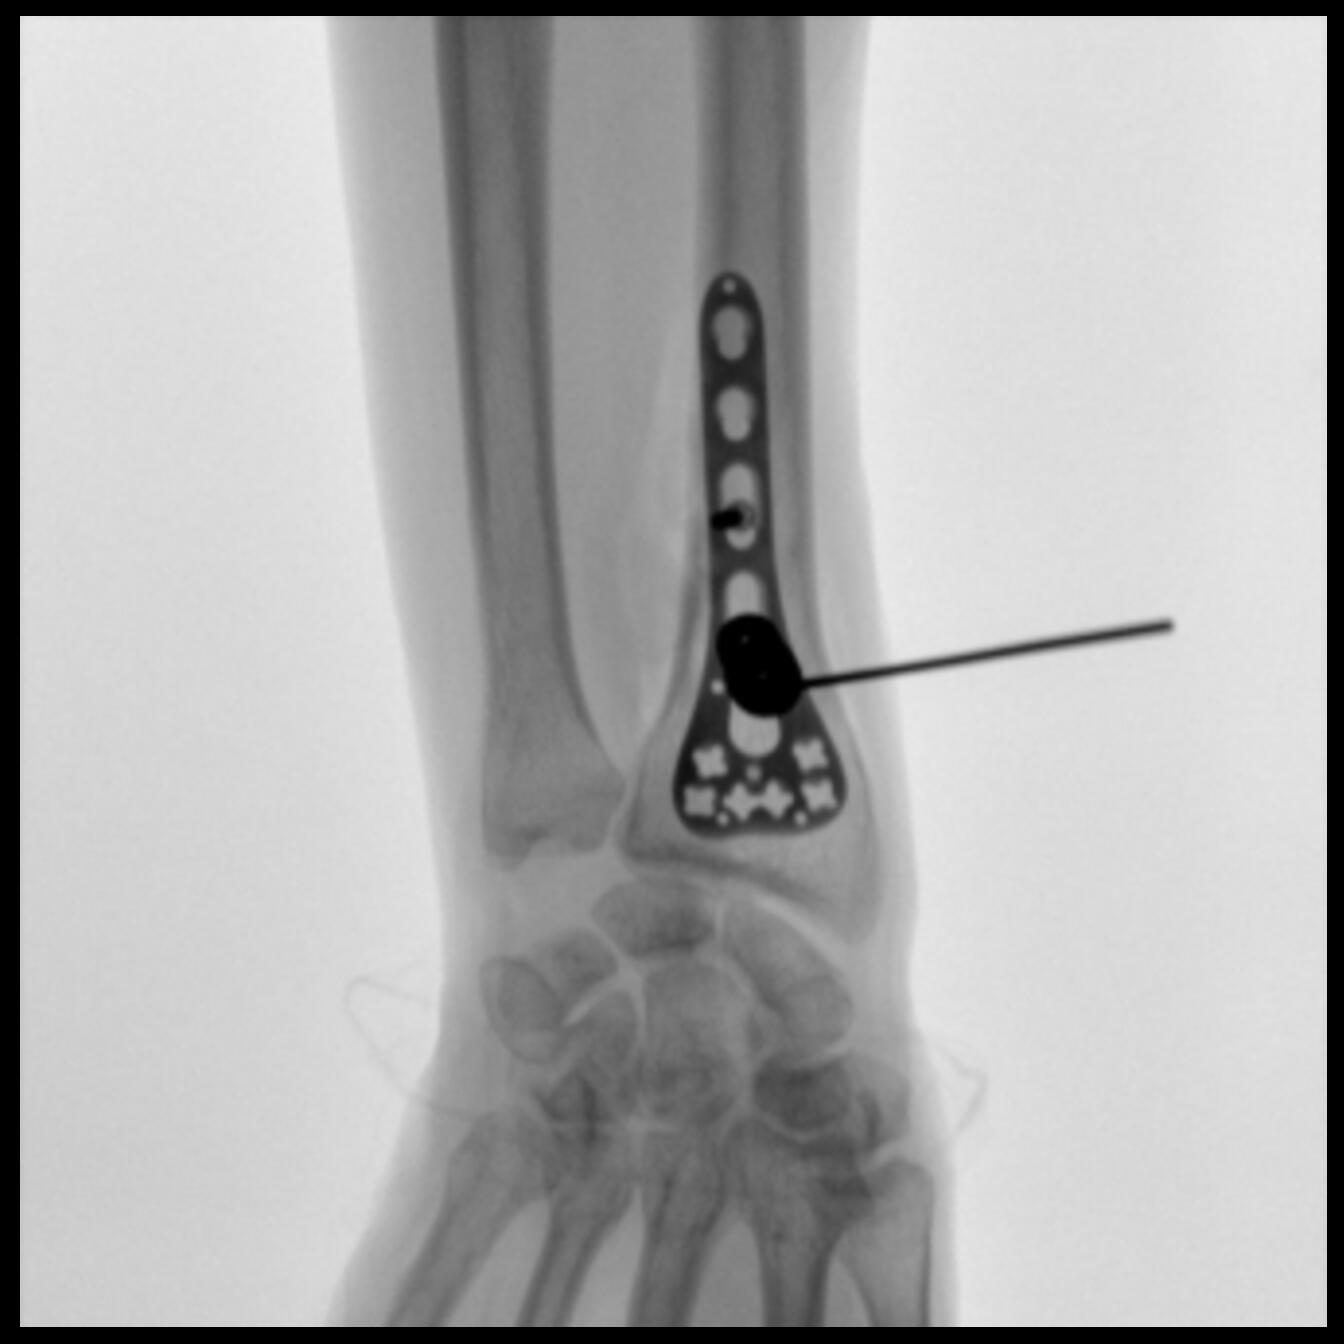

Clinical picture

臨床圖片